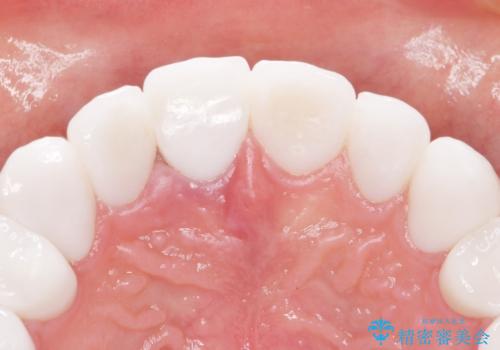

虫歯をしっかりと治療したのち、オールセラミッククラウンによる補綴治療を行いました。

憧れのヴィジュアル系バンドマンのような白い歯になり、喜んで下さいました。

不適なレジン充填によるデコボコがなくなったことで歯磨きしやすくなり、また気にされていた咬み合わせも良くなり、ご満足頂けました。

クラウンの種類:オールセラミッククラウン スタンダード

シェード:NW0